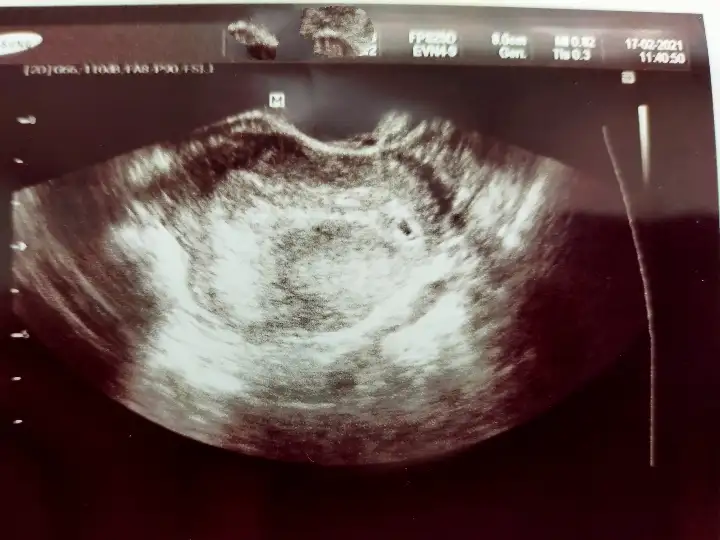

O kadarlıkken benim de görünmemişti normalBenimde dün gördük canım keseyi sat a göre dün 4+5 di...yolk saç vs görünmedi ..Ama erken dimi ?

Kız bende attım kese fotosunu görebilirsensayet yorumlarmisin?4+5 adetine göre dedin herhalde. Crl ölçmemiş çünkü. Bide küçük ölçmüş o çentikler hiç uçtan uca değil. Dr'unu değiştir bence. Bu sefer küçük ölçer, bidahakine büyük ölçer boş yere kafa karışıklığıBenim ilk gittiğim de büyük ölçmüştü. Yani öyle ölçmek için kör olmak lazımdı

Bakiyim canımKız bende attım kese fotosunu görebilirsensayet yorumlarmisin?

Kese 4 mm yakın ölçmüş ama ben ölçüm çentiğini göremedim canım. Kesenin etrafı iyi kalınlaşmış aslında. Günü için de 5+1 demiş ama kese 4 mm iken 5+1 olamaz. Onu nasıl hesaplamış cihaz anlamadımBilmiyorum ki canım kaç olmadı gerektiğini Dr bı kızardı bozardi zaten bende birşey soramadım yarın tekrar gel dedi

Kese 4mm iken kaç haftalık olur 4mu evet çentikli değil ne biliyom nasıl ölçtü kesenin etrafının iyi kalınlaşması nedir ben zaten hiç birşey anlamadım keseyi gorecem diye zaten aleti içimde bı ora bı bura gezdirdi canımda yandı saklanmış dedi anlamadim dış gebelik olabilirmi?Kese 4 mm yakın ölçmüş ama ben ölçüm çentiğini göremedim canım. Kesenin etrafı iyi kalınlaşmış aslında. Günü için de 5+1 demiş ama kese 4 mm iken 5+1 olamaz. Onu nasıl hesaplamış cihaz anlamadım![]()

Yok ya ben gördüm. sağda yukarda. Yani etrafı iyi kalınlaşmış demek iyi tutunmuş. 4 mm kese tam kaçıncı güne tekabul eder bilmiyorum canım ama 5+1'den ufaktır.Kese 4mm iken kaç haftalık olur 4mu evet çentikli değil ne biliyom nasıl ölçtü kesenin etrafının iyi kalınlaşması nedir ben zaten hiç birşey anlamadım keseyi gorecem diye zaten aleti içimde bı ora bı bura gezdirdi canımda yandı saklanmış dedi anlamadim dış gebelik olabilirmi?